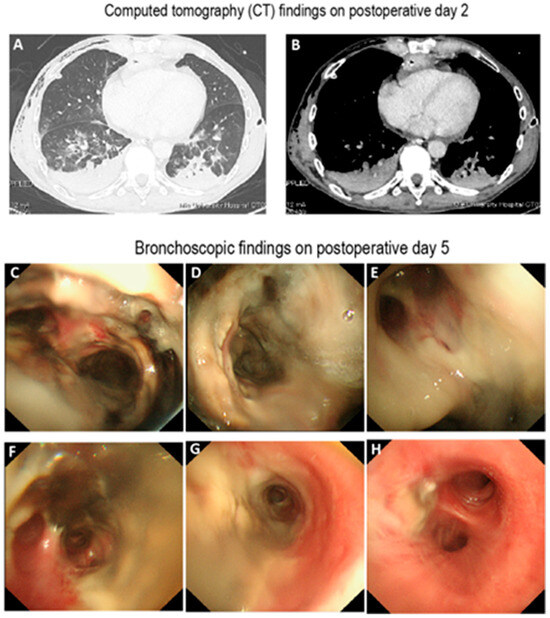

Background: Meningoencephalitis is a complex inflammatory condition of the CNS that can result in significant morbidity and mortality in critically ill adults. Accurate and timely neuromonitoring is essential for guiding management and improving outcomes. This study aimed to descriptively evaluate the prognostic value of early TCCD monitoring, particularly the pulsatility index, and its integration with conventional and perfusion MRI in patients with meningoencephalitis. Methods: We present an observational, retrospective, cohort study involving ten adult patients (median age 56 years, IQR 45.5–68.5; mean 55.9, range 35–76) with neurological syndromes caused by suspected or confirmed infectious meningoencephalitis. Etiologies included bacterial meningitis/meningoencephalitis (50%), viral meningoencephalitis (10%), neurotoxoplasmosis (10%), progressive multifocal leukoencephalopathy (10%), and undetermined origin (20%). Patients underwent TCCD and MRI within 24 h. In five cases, standard MRI sequences were acquired, while in the remaining five, perfusion imaging was performed using Arterial Spin Labelling (ASL). A favorable outcome was defined as survival with neurological recovery (Glasgow Outcome Scale > 5) at ICU discharge. Results: TCCD-derived PI provided valuable information on cerebral hemodynamics. PI values ≤ 1.25 were associated with favorable clinical outcomes and symmetrical MRI findings. Conversely, PI > 1.25 correlated with poor prognosis and often preceded MRI-detectable structural damage. When combined with ASL, PI mirrored the detected perfusion asymmetries and was associated with poor prognosis in fatal cases. Conclusions: Bedside TCCD can offer real-time assessment of cerebrovascular dynamics and, when integrated with conventional and ASL MRI, could enhance the understanding of pathophysiological processes in meningoencephalitis, supporting timely and informed decisions in neurocritical care.